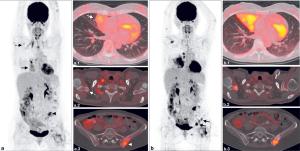

Melanoma of the skin is the 19th most common malignant neoplasm worldwide, with 287,723 new cases estimated for 2018 and metastatic melanoma accounting for 4% of all new cases. In recent years, the prognosis of this stage has undergone a dramatic transformation with the advent of immunotherapy and BRAF/MEK targeted therapy.